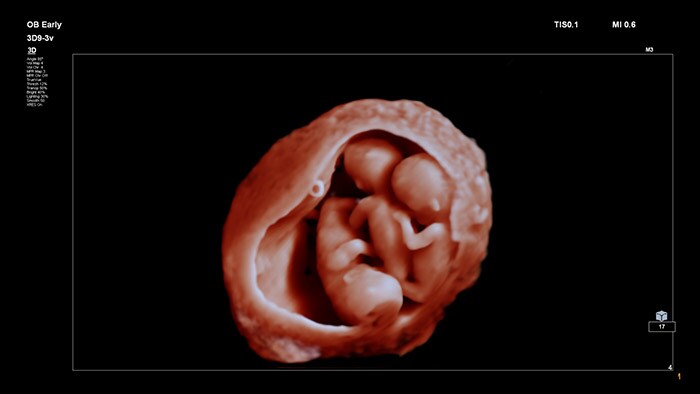

With innovative, highly detailed images and the ability to manipulate a flexible virtual light source, TrueVue provides clinicians and expecting mothers with incredibly lifelike images of the fetus during pregnancy.